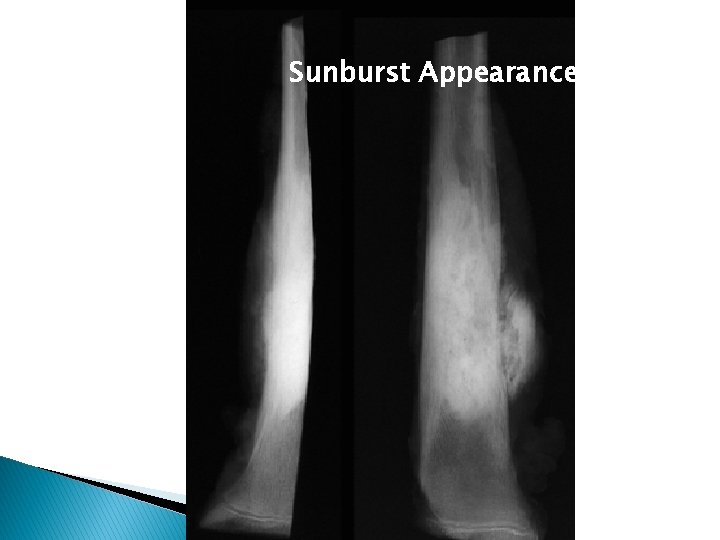

Sunburst Appearance

Osteosarcoma � � � Variable with combination of bone destruction and bone formation Sun ray spicules/ sun burst appearance and Codman’s triangle may be evident Cortical breach common Adjacent soft tissue mass Joint space rarely involved ◦ 25% Lytic ◦ 35% Sclerotic ◦ 40% Mixed � Telangiectatic type- purely lytic